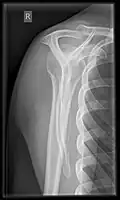

Shoulders

AP glenoid (Grashey view).

These include:

AP-projection 40° posterior oblique after Grashey

The body has to be rotated about 30 to 45 degrees towards the shoulder to be imaged, and the standing or sitting patient lets the arm hang. This method reveals the joint gap and the vertical alignment towards the socket.[17]

In the UK, the standard projections of the shoulder are AP and Lateral Scapula or Axillary Projection.[15]

Extremities

A projectional radiograph of an extremity confers an effective dose of approximately 0.001 mSv, comparable to a background radiation equivalent time of 3 hours.[16]

• Clavicle - AP and AP Cranial

• Humerus - AP and Lateral